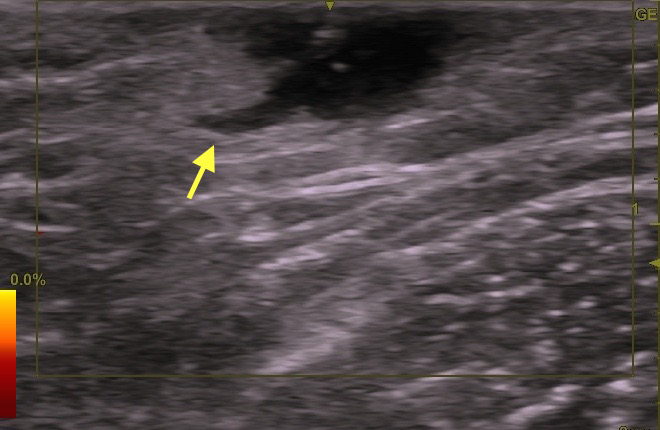

下写真のケースの場合は、矢印の所が開口部です。

右写真のエコーで確認できます(→)。その下に本体がいます。